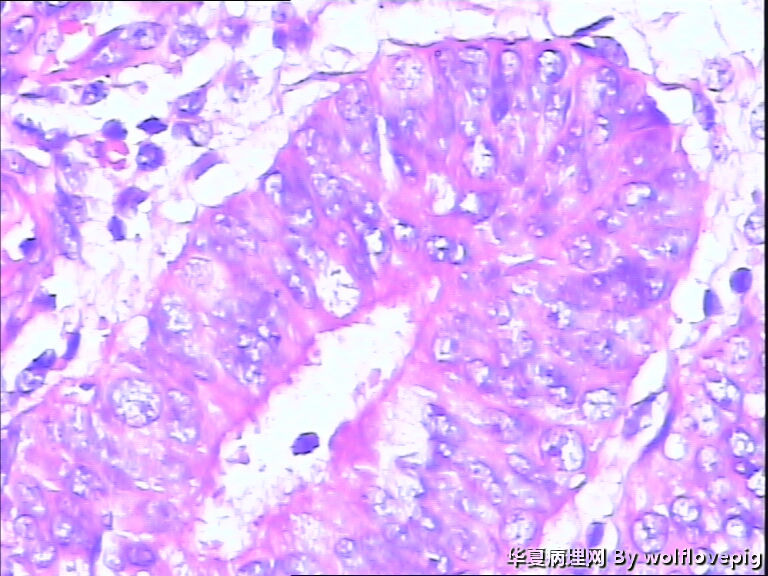

48y

子宫内膜复杂性非典型增生(有没有癌变,待制作优良的切片再诊断吧)。

复杂性非典型增生

子宫内膜复杂性非典型增生

复杂性非典型增生(EIN)